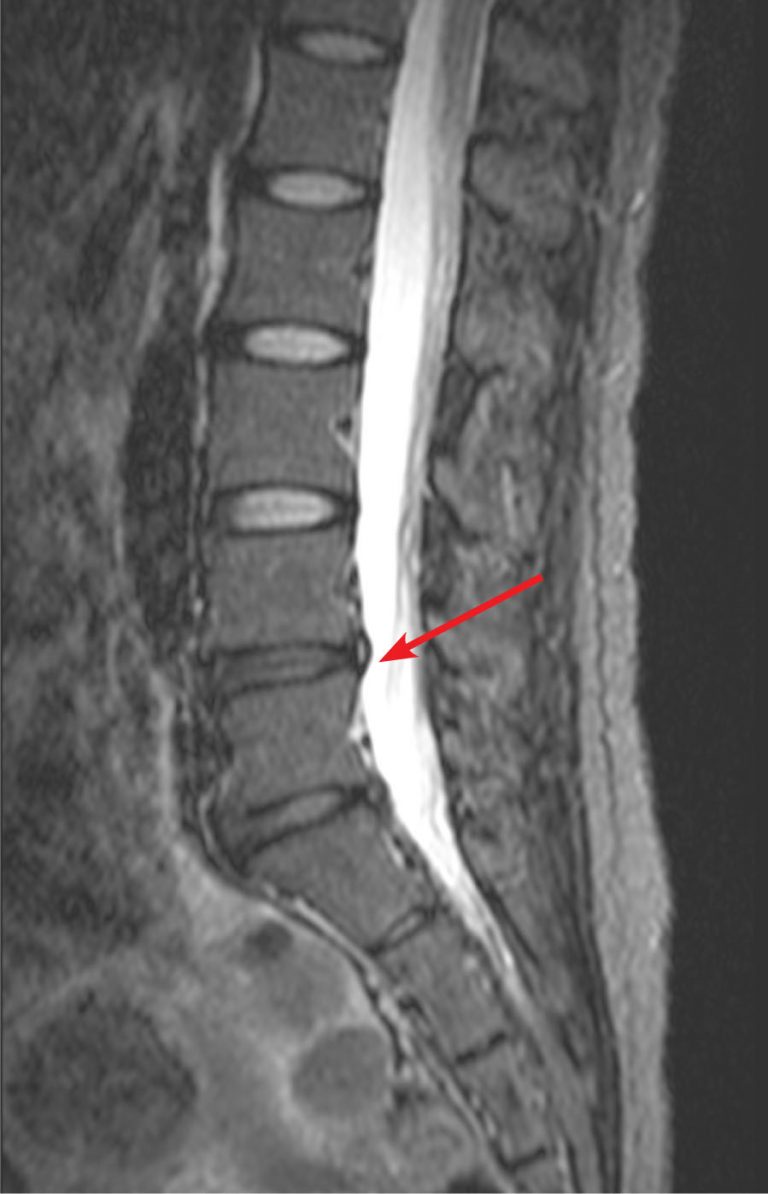

Annular tear in lumbar spine YouTube How To Heal Annular Disc Tear  An annular tear can be extremely painful because the outer third of the. Outline the evaluation in patients with annular disc tears. If these treatments do not help.  when a tear occurs, and no disc material is ruptured, it is called an annular tear.   describe the etiology, pathophysiology, and complications of annular disc tears. Gentle exercises to strengthen. How To Heal Annular Disc Tear.

Lumbar Disc Annular Tear How To Heal Annular Disc Tear    healing time for annular tear varies from patient to patient. Gentle exercises to strengthen back muscles and improve flexibility.  when a tear occurs, and no disc material is ruptured, it is called an annular tear.   physical therapy treatment for annular fissures includes exercises, traction, and other therapies. Outline the evaluation in patients with annular disc tears. . How To Heal Annular Disc Tear.